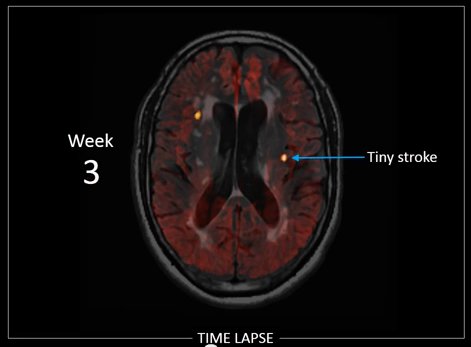

Un fermo-immagine dal video che illustra lo studio, visibile alla fine dell'articolo.I ricercatori del Centro di Neuroscienze Krembil hanno potenzialmente scoperto una causa importante di demenza.

I ricercatori hanno condotto uno studio approfondito per osservare lo sviluppo di questa malattia della sostanza bianca in un breve periodo di tempo, piuttosto che su base annuale, che è l'intervallo con cui gli studi precedenti avevano eseguito le scansioni del cervello. Lo studio ha coinvolto 5 pazienti con la malattia della sostanza bianca che si sono sottoposti ad una scansione MRI dettagliata del cervello, ogni settimana per 16 settimane consecutive.

Le scansioni MRI settimanali hanno rivelato nuove piccole macchie che nascono nella materia bianca del cervello, che in base al loro aspetto MRI, erano caratteristiche di piccoli nuovi ictus (infarti cerebrali). Le lesioni non avevano sintomi, ma, con il tempo, si potevano paragonare alla malattia esistente della sostanza bianca nel cervello dei soggetti. Nel campionamento casuale dello studio, la maggior parte dei soggetti ha avuto questo fenomeno: piccoli ictus che accadono senza sintomi, e diventano quel tipo di malattia della sostanza bianca che causa la demenza.